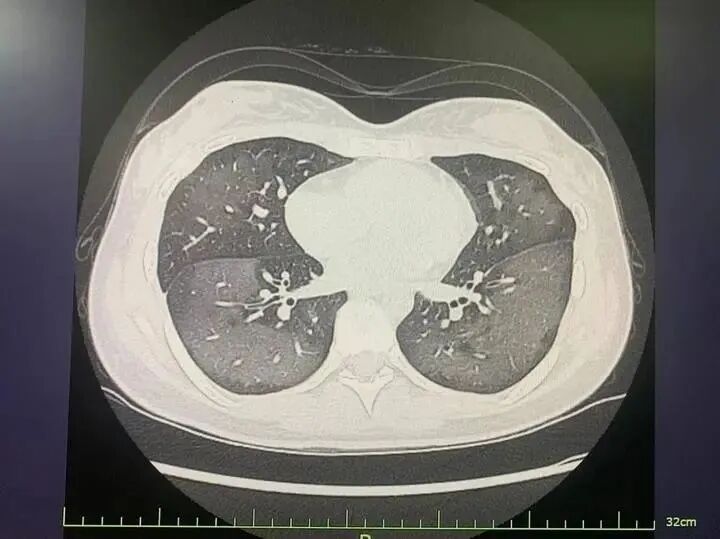

涵涵的胸片结果提示两肺大片斑片影,已接近“白肺”,基本考虑是防晒喷雾吸入后导致急性过敏性肺炎。经入院治疗后,涵涵的病情得以好转。

一个小时过去,她感觉越来越不舒服、呼吸越来越困难。到医院经CT检查发现,丽丽的双肺呈现大范围白色样病变,报告提示“白肺”。被诊断为“急性过敏性肺炎”。